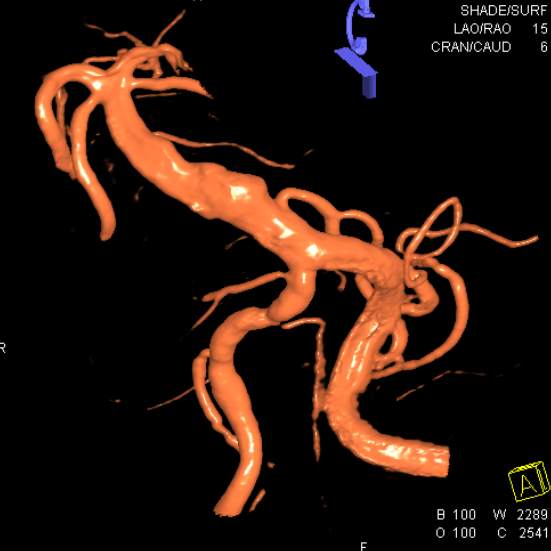

患者男性,34岁,年前自新疆坐车48小时来到我院,诊断:椎基底动脉冗长扩张症,出现脑干压迫症状、后组颅神经症状、部分中组颅神经症状、小脑症状、颅内压增高(220mmHg),症状进行性加重,最大径15mm,血管外面存在血栓造影只能窥见部分,短短两周,病变形态出现明显变化,局部出现明显瘤样凸起(图2-3),手术方案只能临时改变,植入血流导向装置,术后看病人语言、四肢活动均正常,围手术期仍然是一个艰巨的过程,充满了不确定因素,希望患者能安全度过围手术期,早日康复,重返工作岗位~~~